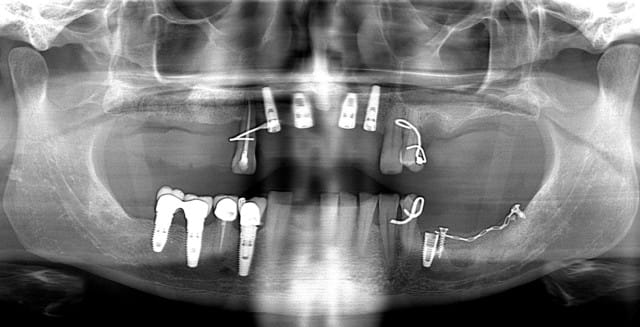

bref un petit rappel:

1 première consultation (septembre 2012)

2 rétro-alvéolaire (septembre 2012)

un an après !

ça s'arrange pas, voyez plutôt..

augmentation de la perte osseuse +++